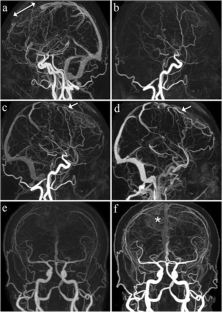

Fig. 1